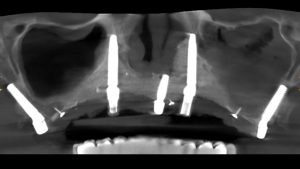

IMPLANTES TRANSNASALES Y CIGOMÁTICOS

El caso que os presentamos en este artículo se corresponde al de una paciente de 67 años que, tras varios intentos fallidos de rehabilitación oral mediante distintas técnicas, acude a nuestra clínica dental en Valencia buscando un tratamiento de implantes viable.